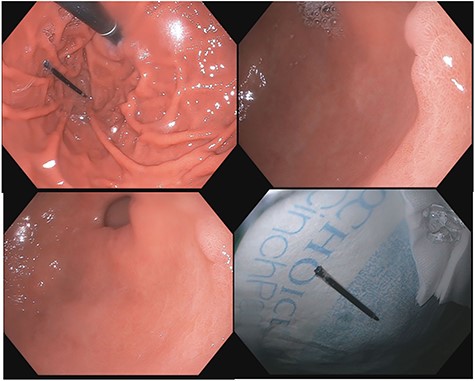

A 43-year-old incarcerated woman with borderline personality disorder and a long history of swallowing various foreign objects in periods of stress presented to the emergency department after swallowing a cup of bleach. Her surgical history was significant for multiple celiotomies for retrievals of purposefully ingested foreign bodies. During evaluation, she also admitted to swallowing an ink pen 3 weeks prior to swallowing the bleach for which she did not seek medical evaluation. She reported no food intolerance or changes in bowel function secondary to swallowing these objects. She presented with mild abdominal pain and cramping, and her vital signs and laboratory investigations were all within normal limits. Her abdominal exam was notable for mild tenderness to palpation diffusely. Computed tomography (CT) of the abdomen (Fig. 4) showed a linear foreign body in the distal gastric antrum penetrating the inferior wall and extending into the adjacent peritoneal fat. No free air or free fluid was appreciated. Initial esophagogastroduodenoscopy (EGD) was significant for mild erythema and edema to the esophageal and duodenal mucosa as a result of the caustic ingestion, and the pen was found to be deeply perforating the stomach antral wall with no associated ulcer or edema (Fig. 1). The depth at which the foreign body was lodged was uncertain, so there was concern for organ involvement outside of the gastric wall. Repeat EGD was done to assess for manifestations of esophageal, gastric or duodenal injuries from her caustic ingestion, and it revealed normal gastric mucosa (Fig. 2). A joint case was planned with the gastroenterology service for endoscopic foreign body retrieval, possible laparoscopic retrieval and gastric repair and possible open retrieval and gastric repair. The patient was taken to the operating room for the third EGD, which revealed spontaneous migration of the foreign body from the perforation site into the lumen of the gastric body (Fig. 3a). Additionally, there was spontaneous closure of the site of previous perforation (Fig. 3b and c). The ink pen was easily removed transorally using an endoscopic snare, and no further surgical intervention was required. After the procedure, the patient reported complete resolution of her abdominal pain and was able to tolerate a regular diet without problems.

EGD on initial presentation; gastric antrum with foreign body perforating through the gastric wall.